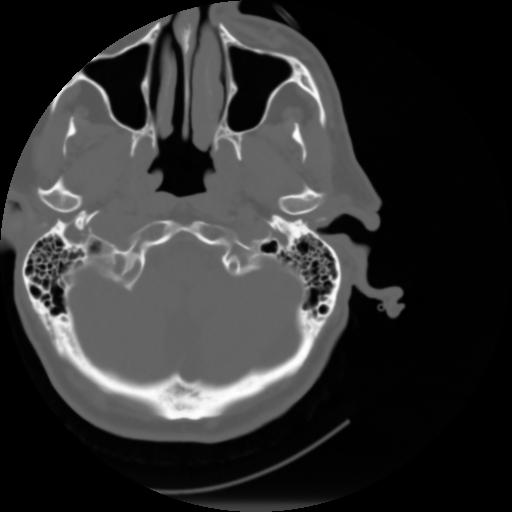

3 CEREBRO,,Axial,3.0,CEREBRO,,